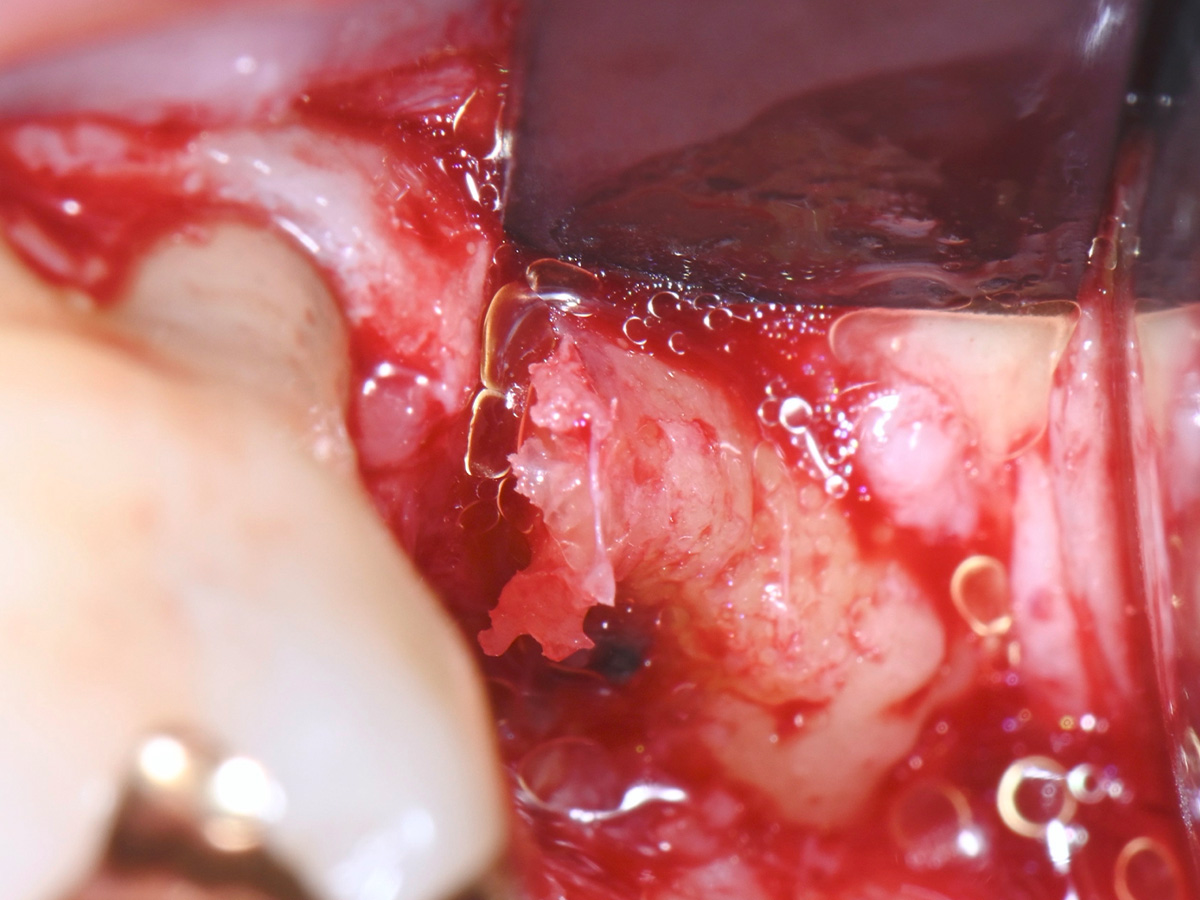

Abbildung 6

Entfernung des entzündlichen Gewebes aus der Extraktionsalveole